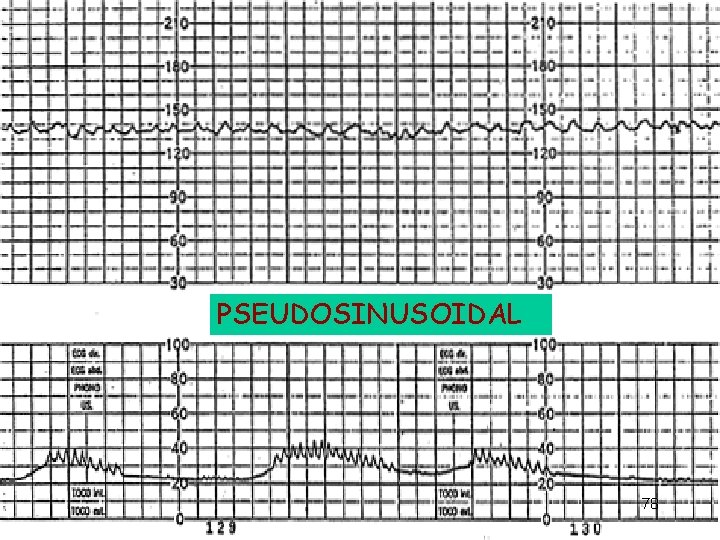

Sinusoidal and Pseudosinusoidal Patterns Sinusoidal pattern: A smooth, undulating pattern, lasting at least 10 minutes with a fixed period of three to five cycles per minute and an amplitude of 5 -15 bpm. Pseudosinusoidal: Usually caused by drugs such as Nubain or Stadol.

PSEUDOSINUSOIDAL 78